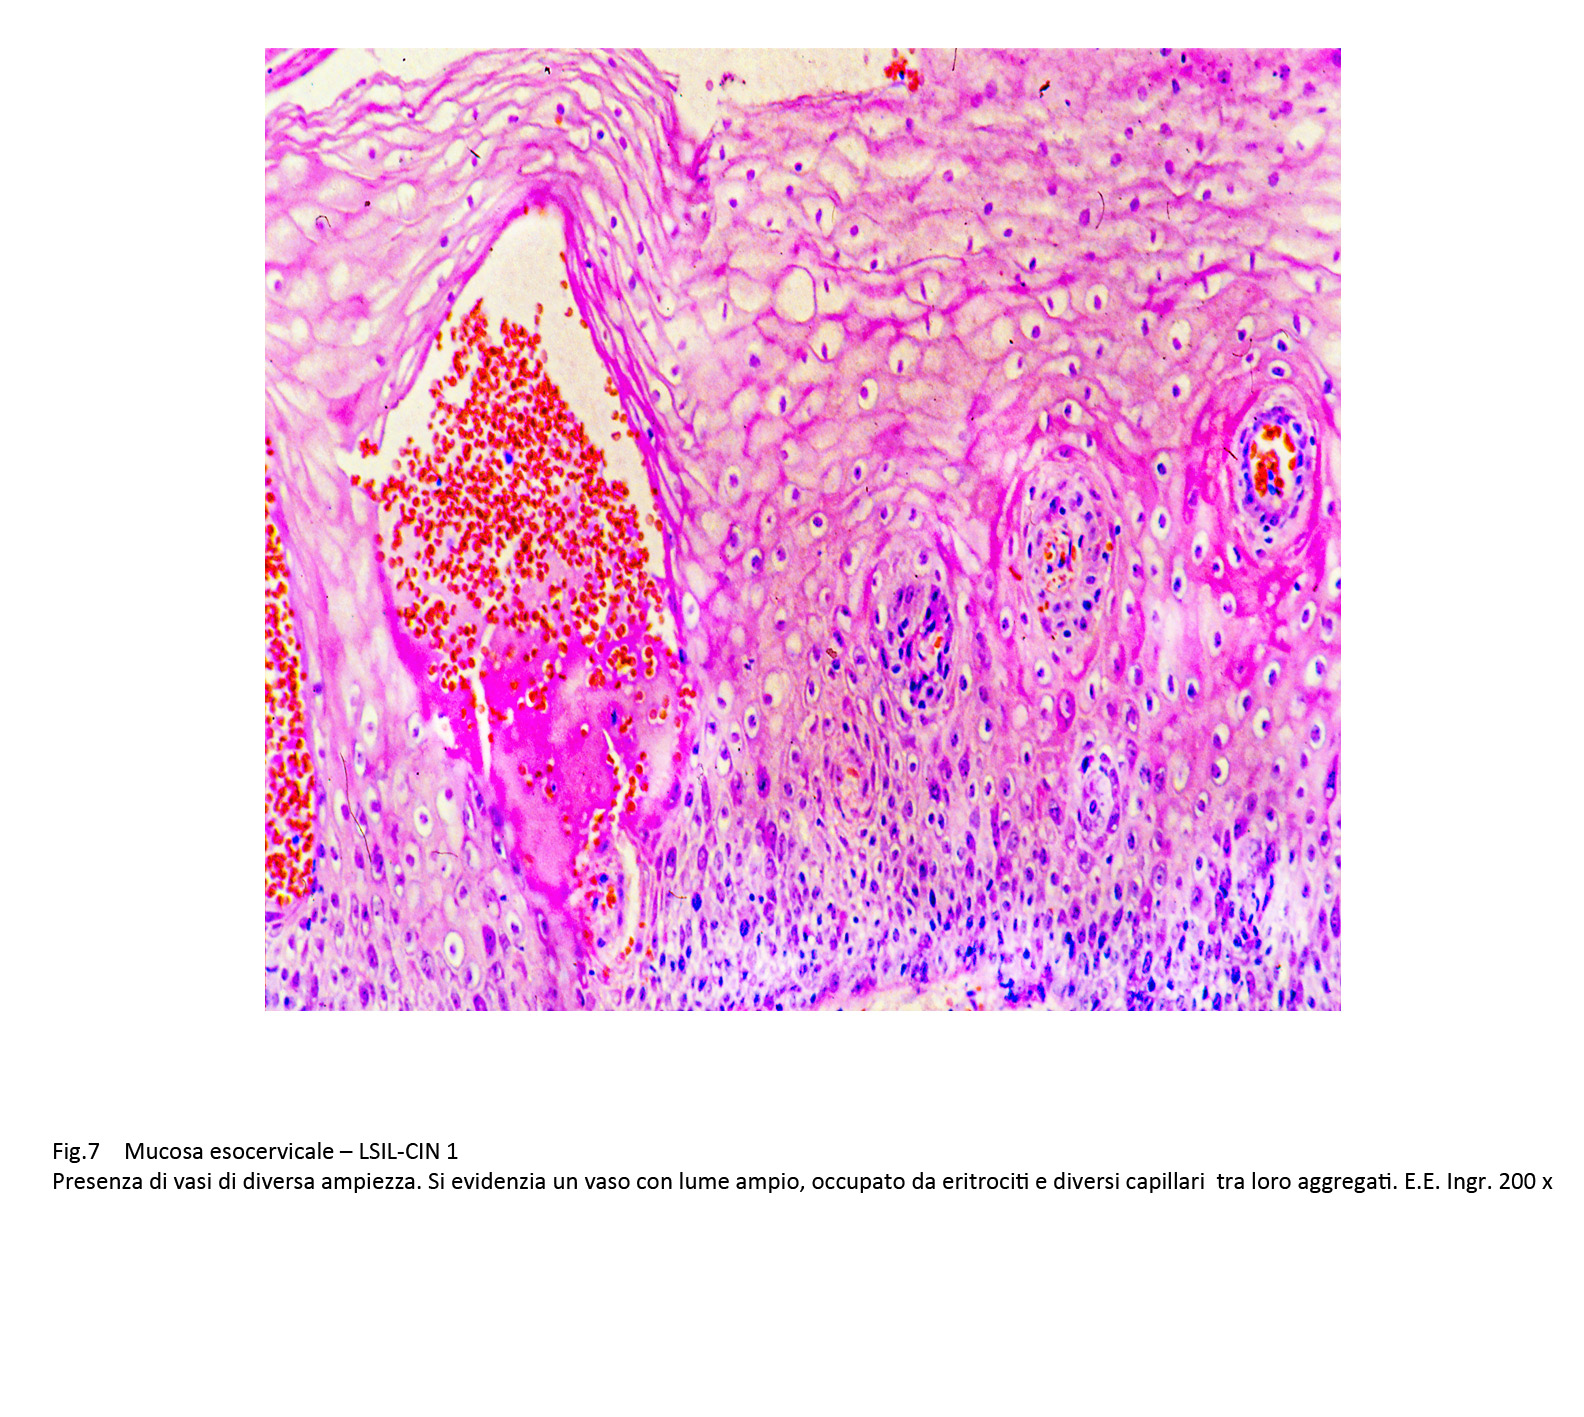

A questo processo proliferativo si associa, spesso, la presenza di vasi neoformati nel contesto degli strati epiteliali a partenza dalla tonaca propria. Abitualmente sono capillari rivestiti solo da elementi endoteliali i quali sono avvolti dagli epiteli in proliferazione; non mancano reperti in cui coesistono nella stessa area vasi con ampio lume e capillari forniti non solo da elementi ma anche da periciti.

Fig.6

Lo stroma sotto-epiteliale appare coinvolto da processi di flogosi e da manifestazioni di neoangiogenesi: La flogosi è sostenuta da elementi mononucleati che si addensano attorno ai capillari e si ritrovano anche tra gli strati epiteliali. I vasi sono rappresentati da capillari spesso avvolti da elementi flogistici o da fibroblasti neoformati. Essi nel loro proliferare si ritrovano anche in sede intraepiteliale, spesso pervenendo agli strati superficiali.

Fig.7

Fig.7part